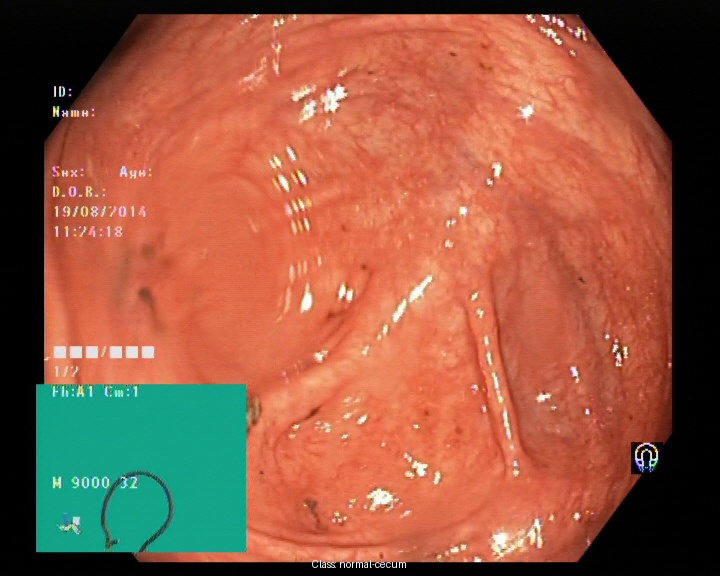

Kvasir dataset serves as a widely recognized resource for research in automated gastrointestinal (GI) disease detection [12]. It contains labeled endoscopic images representing a range of GI conditions, including both healthy and pathological cases. Its diversity in anatomical regions and pathological categories makes it a valuable benchmark for training machine learning models aimed at GI disease classification. The dataset has 8000 images belonging to 8 different classes namely dyed-lifted-polyps, dyed-resection-margins, esophagitis, normal-cecum, normal-pylorus, normal-z-line, polyps, ulcerative-colitis. Figure 1 depicts the sample images from the dataset. Despite its extensive coverage, the dataset poses challenges such as variations in lighting, differences in image quality, and visual similarities between certain categories, which may affect model performance and classification accuracy.

| (a) | (b) | (c) | (d) |

| (e) | (f) | (g) | (h) |